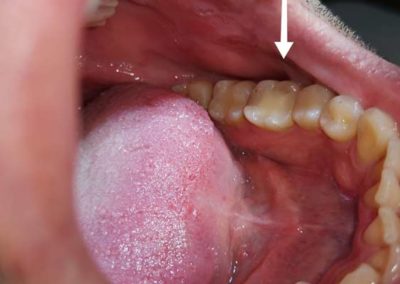

Pacijent se javio zbog otoka u predelu vilice koji se jasno vidi sa spoljne strane obraza. Mesto otoka je bolno i narušava funkciju govora i žvakanja. Zaostali koreni zuba predstavljaju zgodno mesto za akumulaciju bakterija u ustima pa na taj način pogoduju nastanku infekcije. Kada se zaostali koren ukloni, otvoren je put ka izlečenju. Čuvanje zdravlja usta je čuvanje celokupnog zdravlja tela.